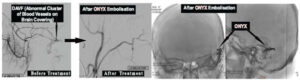

Intra Cerebral Hemorrhage(ICH) is one of type of Brain hemorrhage, which occurs in the substance of Brain due to bursting of Brain Venous system because of high flow and pressure into them exerted by Abnormal cluster of blood vessels on Brain Covering (Duramater). With Interventional Neuroradiological Techniques,Without opening the Skull ; these Abnormal cluster of blood vessels on Brain Covering can be treated by various technique e.g.: ONYX , Glue Embolisation etc.

Example : 35 Yrs. old gentleman presented with severe headache & loss of Consciousness due to Brain hemorrhage from Brain DAVF. After ONYX Embolisation of Brain DAVF ,he recovered completely.